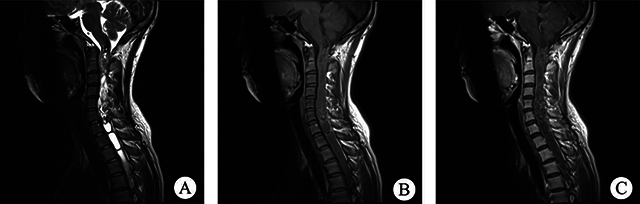

脊髓柔毛细胞星形细胞瘤(PA)是一种罕见疾病,具有不典型的临床和影像学特征,一般仅限于病例报告。我们分析了2010年1月至2021年7月期间收治的12例脊髓PA患者的临床表现、影像学结果、治疗和预后随访,并回顾了相关文献。放射学评估,尤其是磁共振成像,有助于提供有效的诊断信息。本文讨论了该疾病的诊断和鉴别方法,试图为更全面的术前评估做出贡献。

Spinal pilocytic astrocytoma (PA) is a rare disorder with atypical, clinical and imaging characteristics, and generally limited to case reports. We analysed the clinical manifestations, imaging findings, treatment and prognostic follow-up of 12 patients with spinal PA admitted from January 2010 to July 2021, and reviewed the relevant literature. Radiological assessment, especially magnetic resonance imaging, can help to provide effective diagnostic information. The diagnosis and differentiation of this disease is discussed in an attempt to contribute to a more comprehensive preoperative assessment.